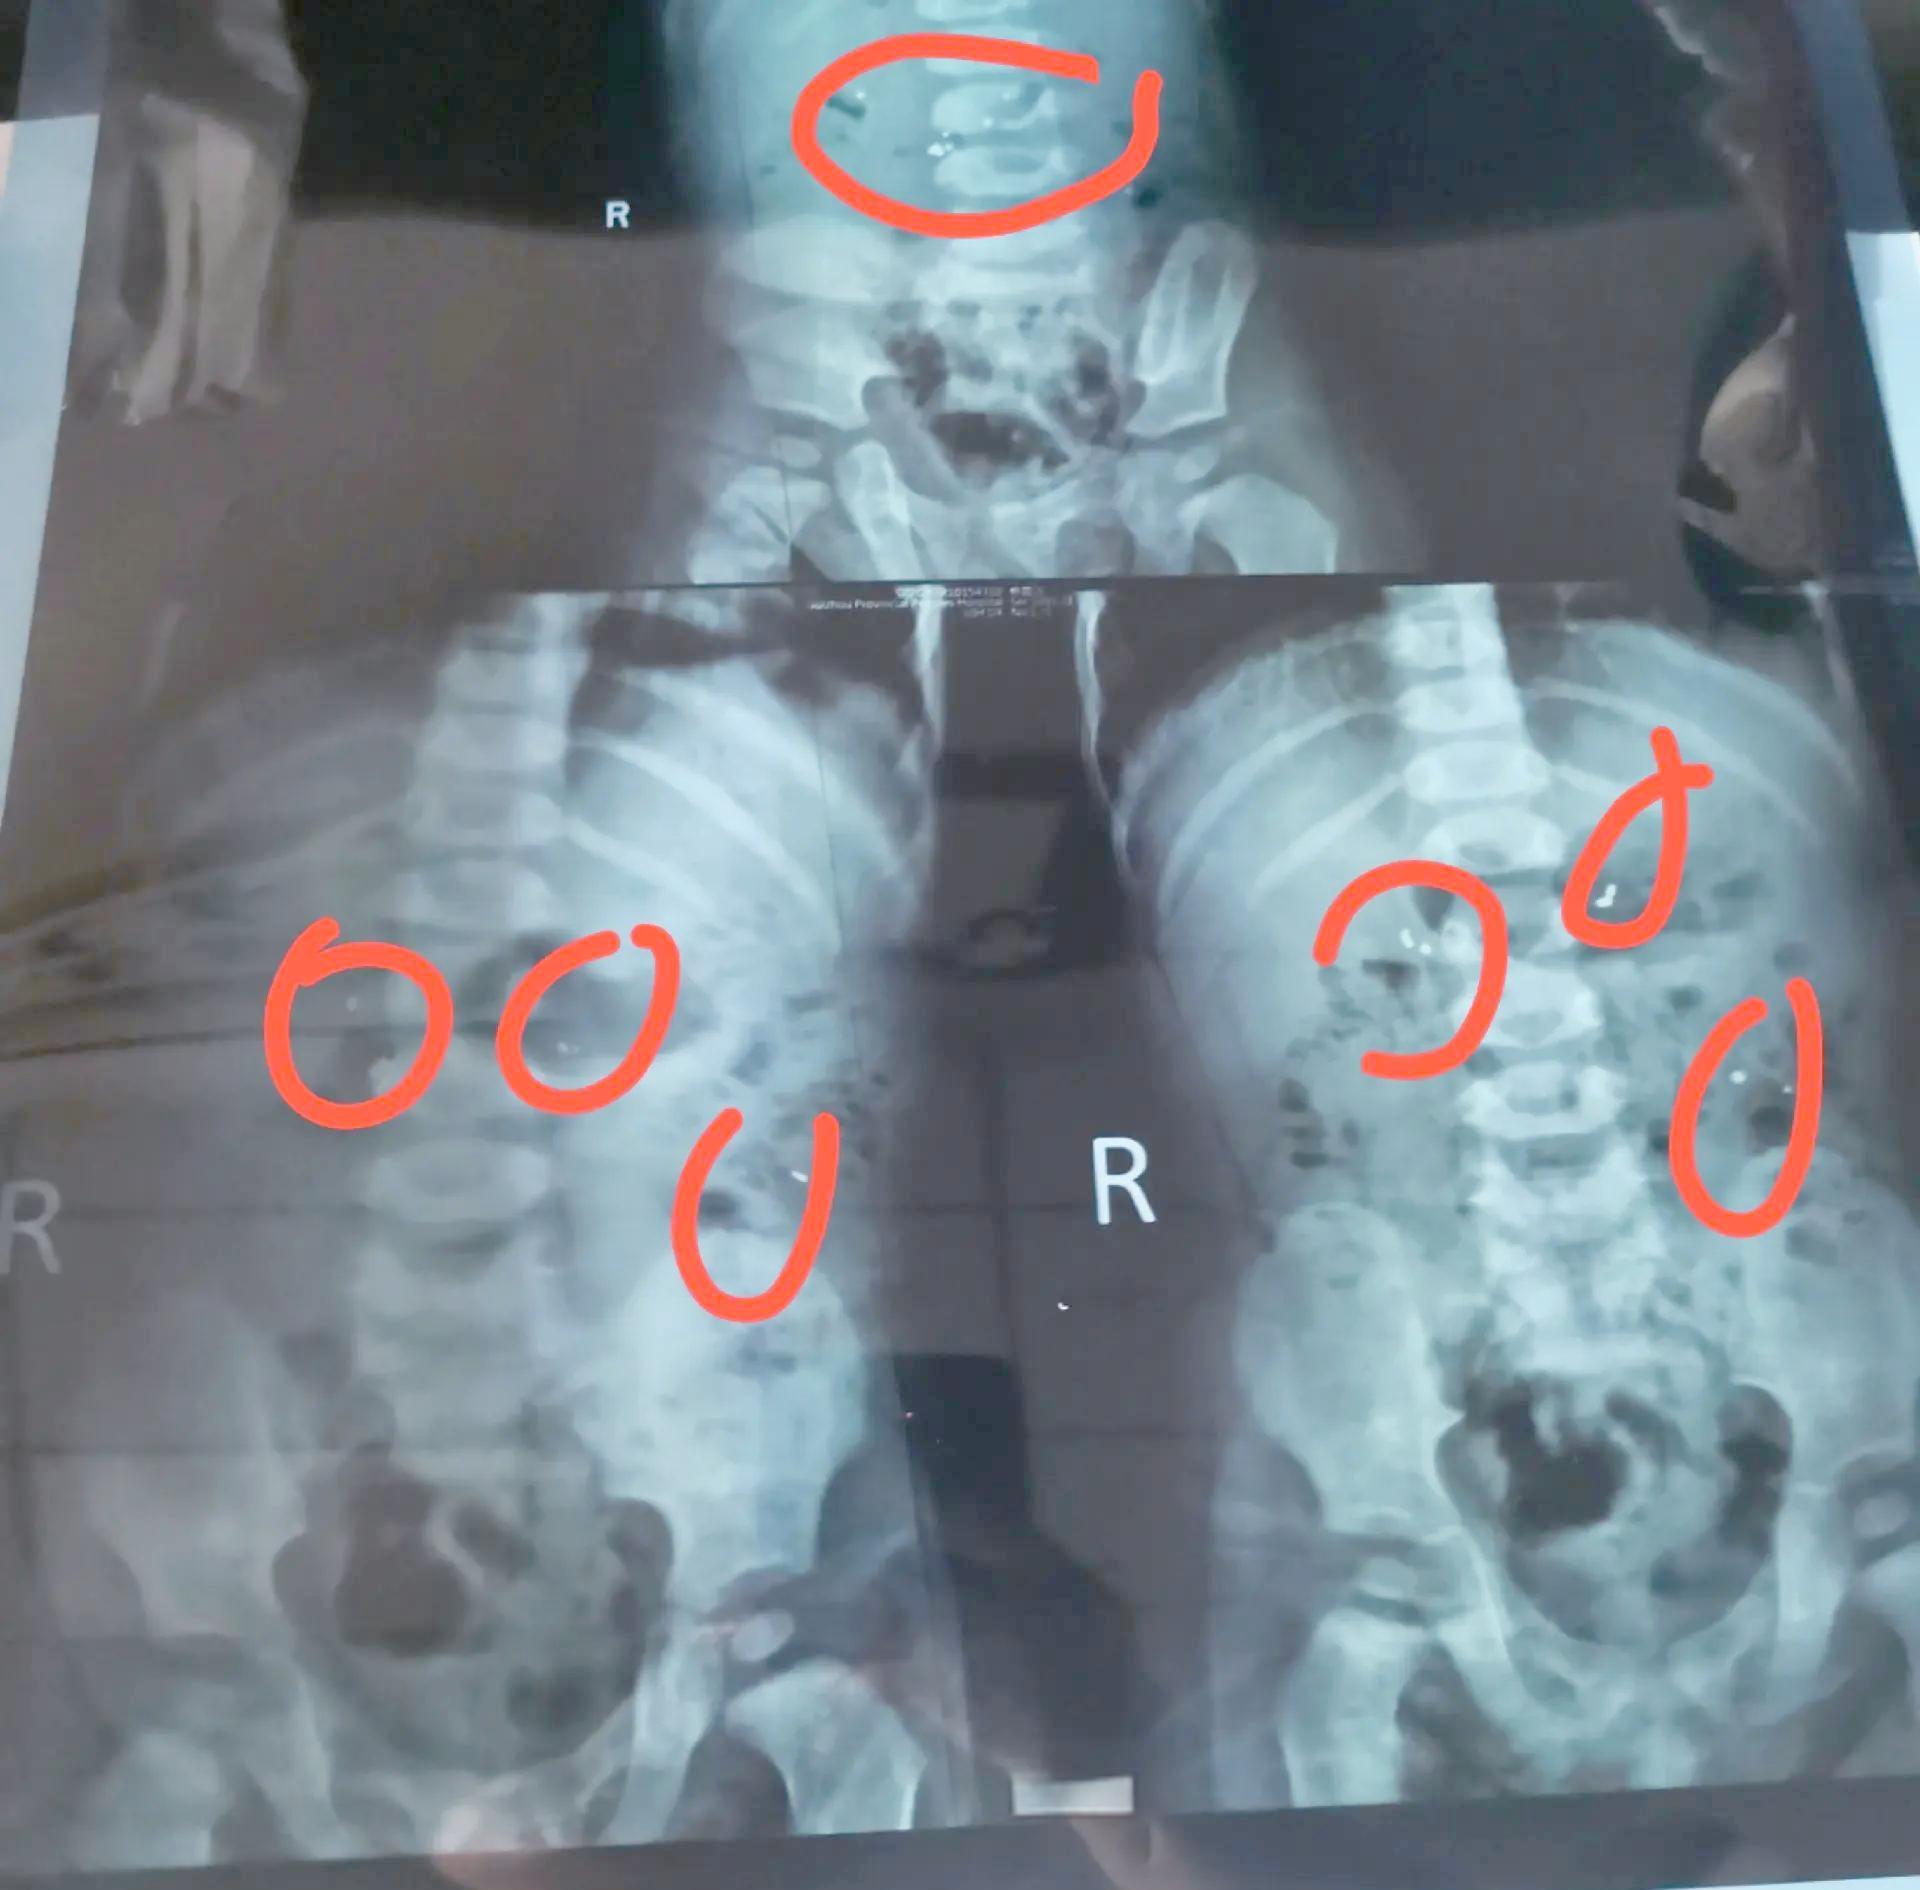

爲什麼連續幾天都肚子疼呢?帶着孩子去醫院一查才發現,這個孩子吞進去的水銀不是通過大便排出體外,而是悄悄地跑到孩子的闌尾,導致孩子闌尾發炎。

醫生就跟家長說要馬上動手術,把裏面的水銀取出來,後來也是通過動手術把裏面的水銀取了出來,孩子的肚子纔不疼。

這樣的一個真實的案例告訴我們,孩子不小心吞進水銀的話確實是要多喝牛奶,這一步沒有錯,但是去醫院檢查也是必要的,畢竟我們不確定這個水銀是在孩子的胃腸道還是在其他的地方,如果說在闌尾這些地方可能就要進行手術了。

就像孩子吞了水銀之後去醫院檢查,最主要的目的是看這些水銀到底在哪裏?如果只是在胃腸道的話,多喫一些高膳食纖維的食物促進腸道的蠕動,確實能夠讓水銀排出來。

如果這些水銀在其他地方,比如說在闌尾,可能就要儘快手術取出來,否則在孩子的體內久了可能對孩子的身體造成很大的負面影響。